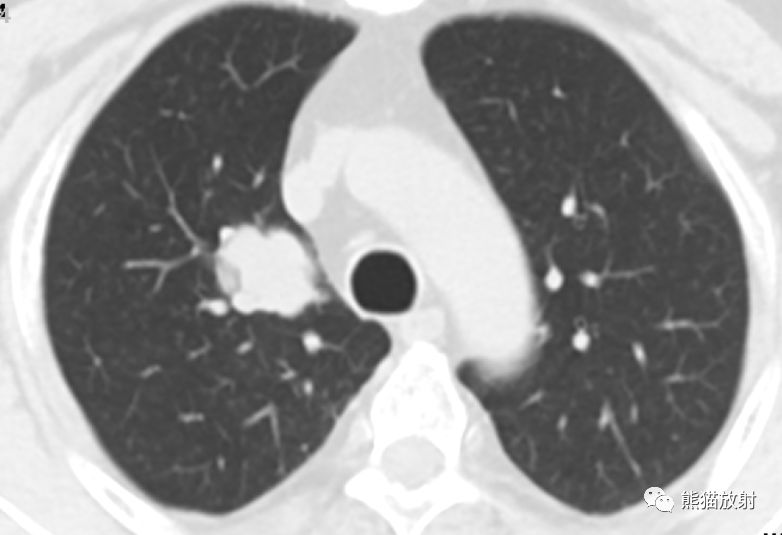

女,55岁,左下肺黏液腺癌。

左下肺孤立性结节,可见浅分叶、毛刺征、血管集束征、空气支气管征;增强扫描实性部分呈轻到中度渐进性强化,中心轻度坏死。